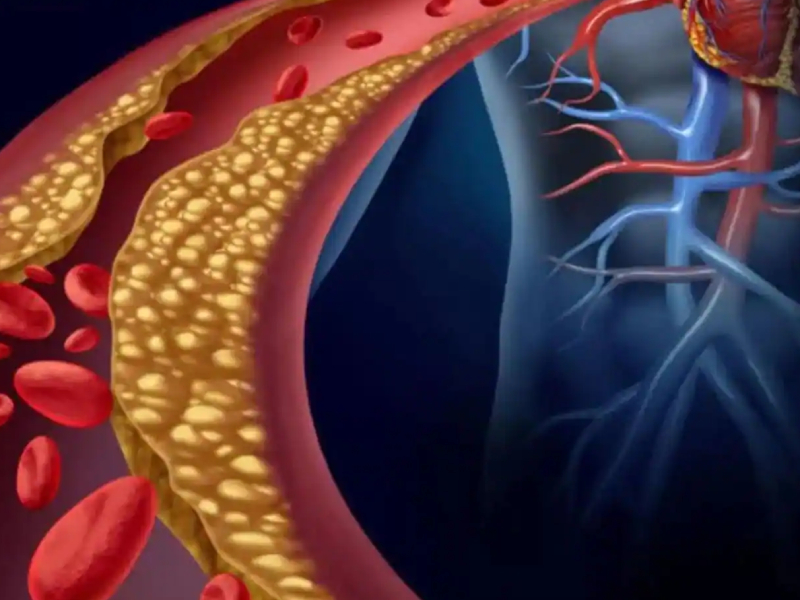

Heart disease is a broad term used to refer to a range of conditions that affect your heart. It includes blood vessel diseases like coronary artery disease, heart rhythm problems or arrhythmias, congenital heart defects and dilated cardiomyopathy among ot